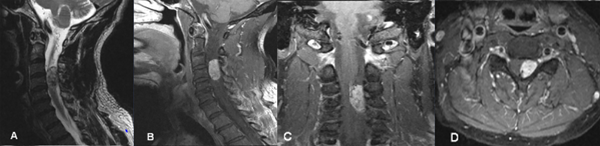

Fig 1. Caso 1. RMN: T2 sagital (A) y T1 con contraste sagital (B) coronal (C) y axial (D) que evidencia lesión nodular intradural extramedular C3-C4 a izquierda, con realce homogéneo post contraste que desplaza y comprime la médula en sentido lateral.

Fig 2. Caso 1. Angiografía cervical espinal evidenciando “blush” tumoral con aferencia primaria de arteria espinal posterior (A, B y C).